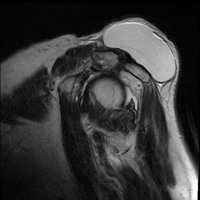

On physical examination, an AC joint cyst is a palpable fluid-filled mass. MRI scanning or a shoulder arthrogram should be obtained to evaluate the shoulder. Unenhanced MRI scans showing a large rotator cuff tear, a degenerated AC joint, and a large subcutaneous cyst adjacent to the AC joint is virtually patognomonic for the disease. Contrast administration on MR arthrogram will show the synovial fluid or intra-articular contrast extravasates from the glenohumeral joint into the subacromial bursa, into the AC joint, and then into an overlying cystic mass when a full-thickness rotator cuff tear is present, resembling a geyser spouting upwards.